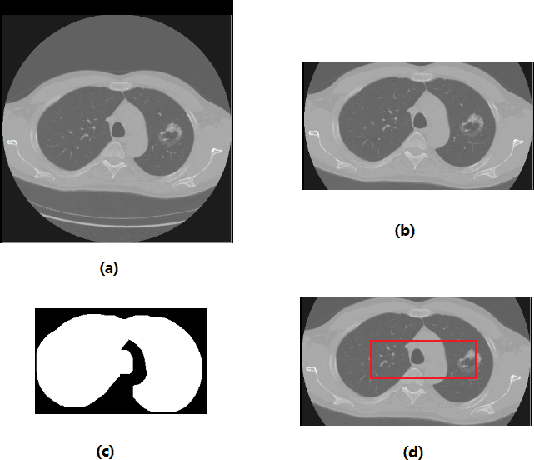

Abstract:We present an automatic COVID1-19 diagnosis framework from lung CT images. The focus is on signal processing and classification on small datasets with efforts putting into exploring data preparation and augmentation to improve the generalization capability of the 2D CNN classification models. We propose a unique and effective data augmentation method using multiple Hounsfield Unit (HU) normalization windows. In addition, the original slice image is cropped to exclude background, and a filter is applied to filter out closed-lung images. For the classification network, we choose to use 2D Densenet and Xception with the feature pyramid network (FPN). To further improve the classification accuracy, an ensemble of multiple CNN models and HU windows is used. On the training/validation dataset, we achieve a patient classification accuracy of 93.39%.